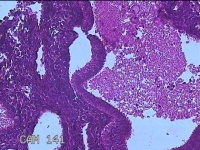

直肠粘膜

性别

男

年龄

57岁

临床诊断

慢性胃炎;胃肠功能紊乱;肠道菌群失调;结肠息肉

一般病史

上腹部胀痛1月余。

标本名称

大体所见

直肠可见多个息肉样隆起,部分表面粗糙。